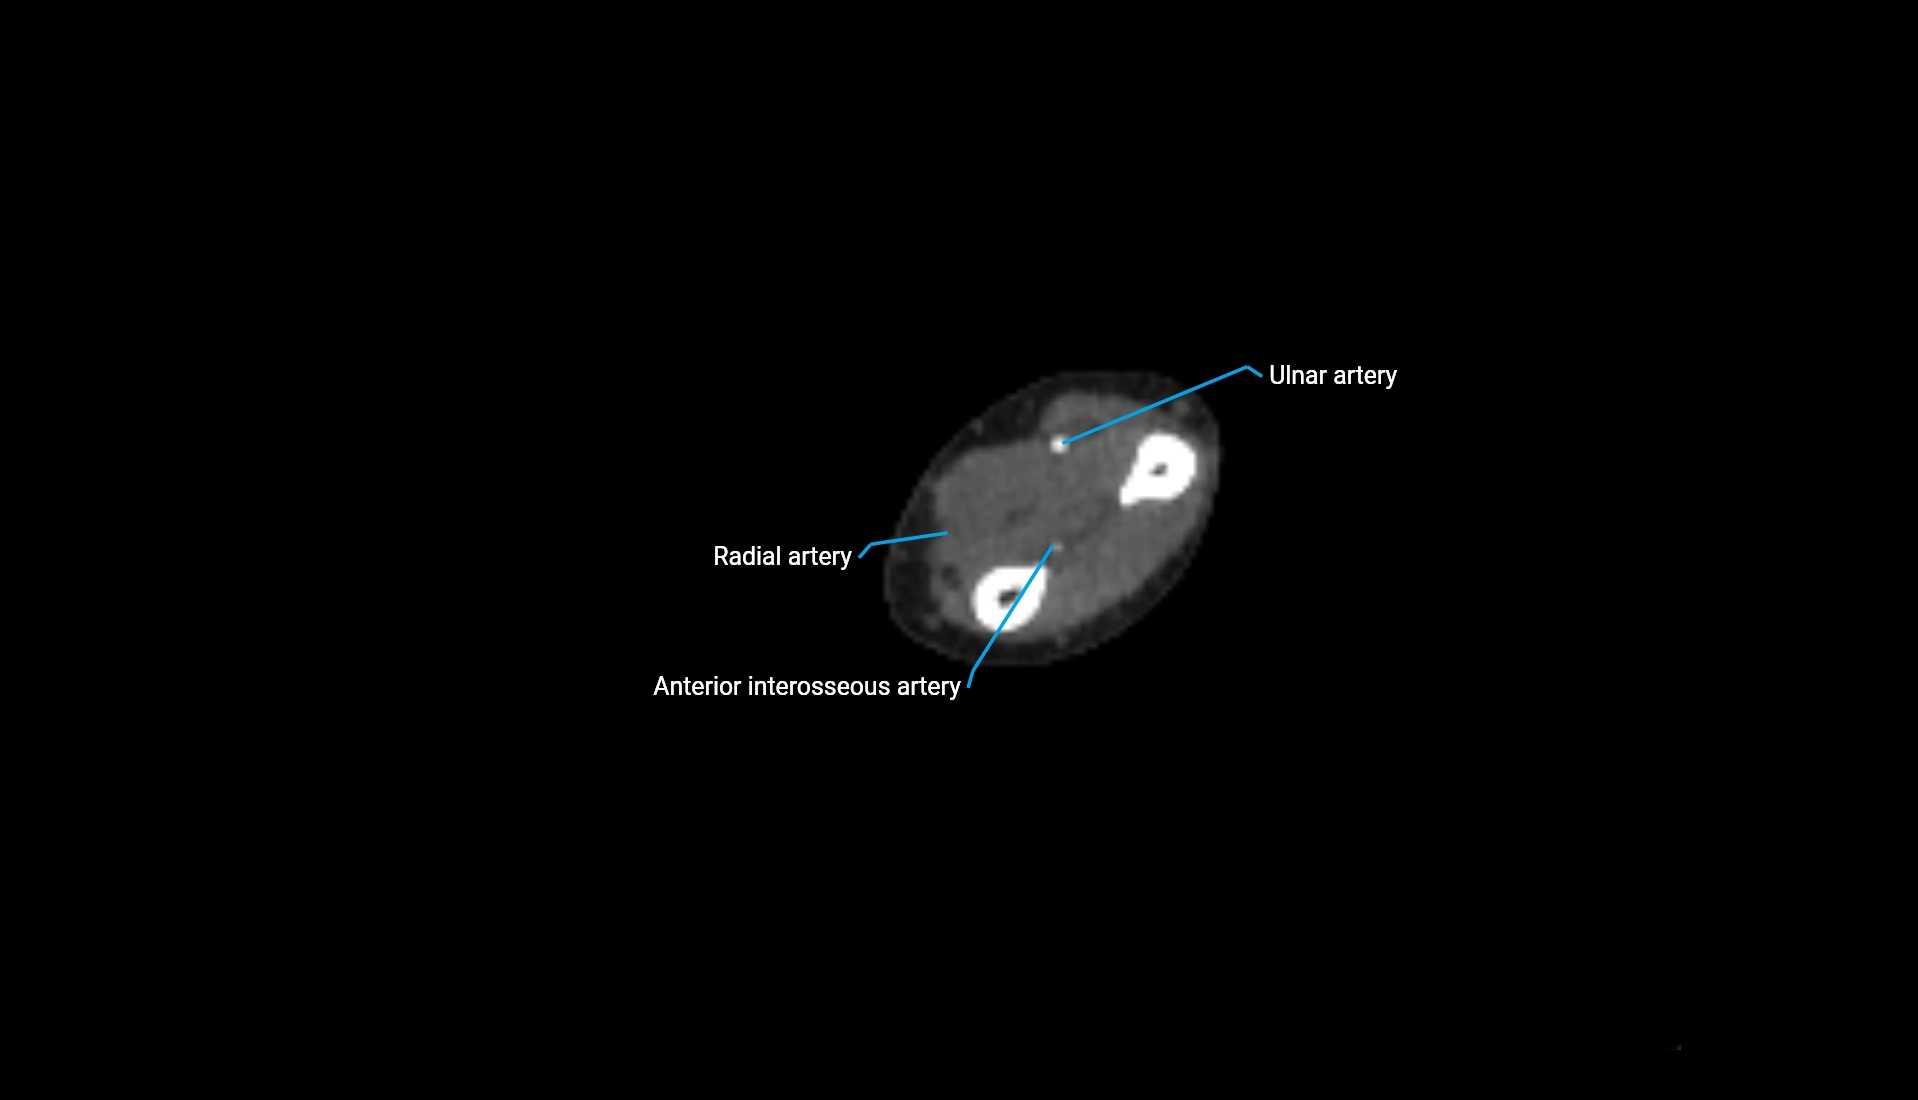

CT Appearance

Non-Contrast CT:

• Cortex: High-density, sharply defined

• Subchondral bone: Dense cancellous matrix

• Articular surface: Smooth concave contour articulating with the capitellum

• Excellent for evaluating bone integrity, alignment, and subtle fractures

Post-Contrast CT:

• Bone: No enhancement

• Joint capsule and synovium: Mild enhancement outlining the joint

• Improves contrast between soft tissues and bony margins

• Useful in detecting subtle joint abnormalities or postoperative changes